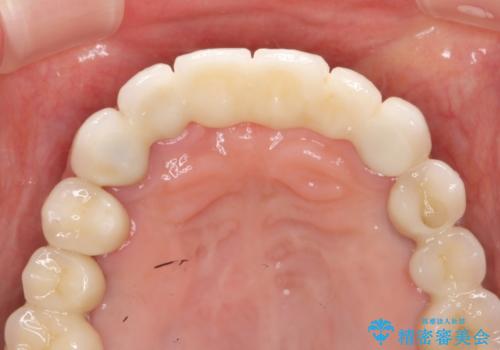

歯周病 全顎治療

- 前歯の見た目、入れ歯による噛めないことの改善を求めて来院されました。

検査により全顎的な歯周病治療、欠損のインプラント補綴、根管治療が必要な状態であることをお伝えし、治療を計画します。

失ってしまった機能を回復し、今後歯を失わないよう残せる歯に歯周病治療を行い、安定した咬合を確立することで長期的に問題なく噛めるような口腔内環境を達成できるようになると考えます。